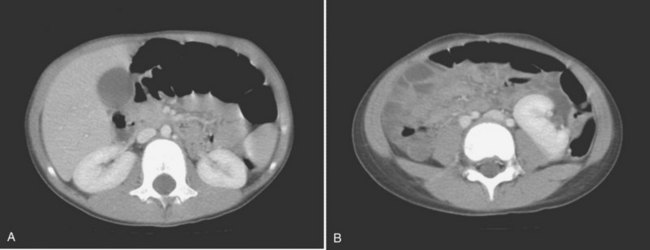

Anomalies of other organ systems are found frequently in affected individuals. The more common sites involve the cardiovascular (30%), gastrointestinal (25%), and musculoskeletal (14%) systems (Emanuel et al, 1974) (Fig. 117–6). They include septal and valvular cardiac defects, imperforate anus and anal or esophageal strictures or atresia, and vertebral or phalangeal abnormalities (Jancu et al, 1976; Wheeler and Weaver, 2001; Rai et al, 2002). Dursun and colleagues (2005) found that 44% of individuals with a congenital solitary kidney, most of whom had URA, had various nonurologic anomalies, but they detected lower incidences of these problems (cardiovascular, 15%; gastrointestinal, 9%; neurologic, 3%; and hematologic, 6%) than previously reported by Emanuel. Chow and colleagues (2005) reported a similar incidence of 42%.

Figure 117–6 Contrast CT scan showing (A) right and left orthotopic kidneys. B, Right midabdominal malrotated supernumerary kidney.

The supernumerary kidney is a distinct mass of renal parenchyma that may be either completely separate or only loosely attached to the major kidney on the ipsilateral side. In about 60% of cases, it is located caudad to the dominant kidney, which is in its orthotopic position in the renal fossa. When a separate and distinct ureter is present, the supernumerary kidney is more likely to be cranial to the dominant kidney but caudal to the adrenal (Bernik et al, 2001). Occasionally, the supernumerary kidney lies either posterior or superior to the main kidney, or it may even be a midline structure anterior to the great vessels and loosely attached to each of the other two kidneys (see Fig. 117–6). The supernumerary kidney may become wedged between the lower poles of a right and left kidney, leading to the radiographic appearance of a “pseudohorseshoe” kidney (Macpherson, 1987). A pelvic supernumerary kidney has also been reported (Eberle et al, 2002).